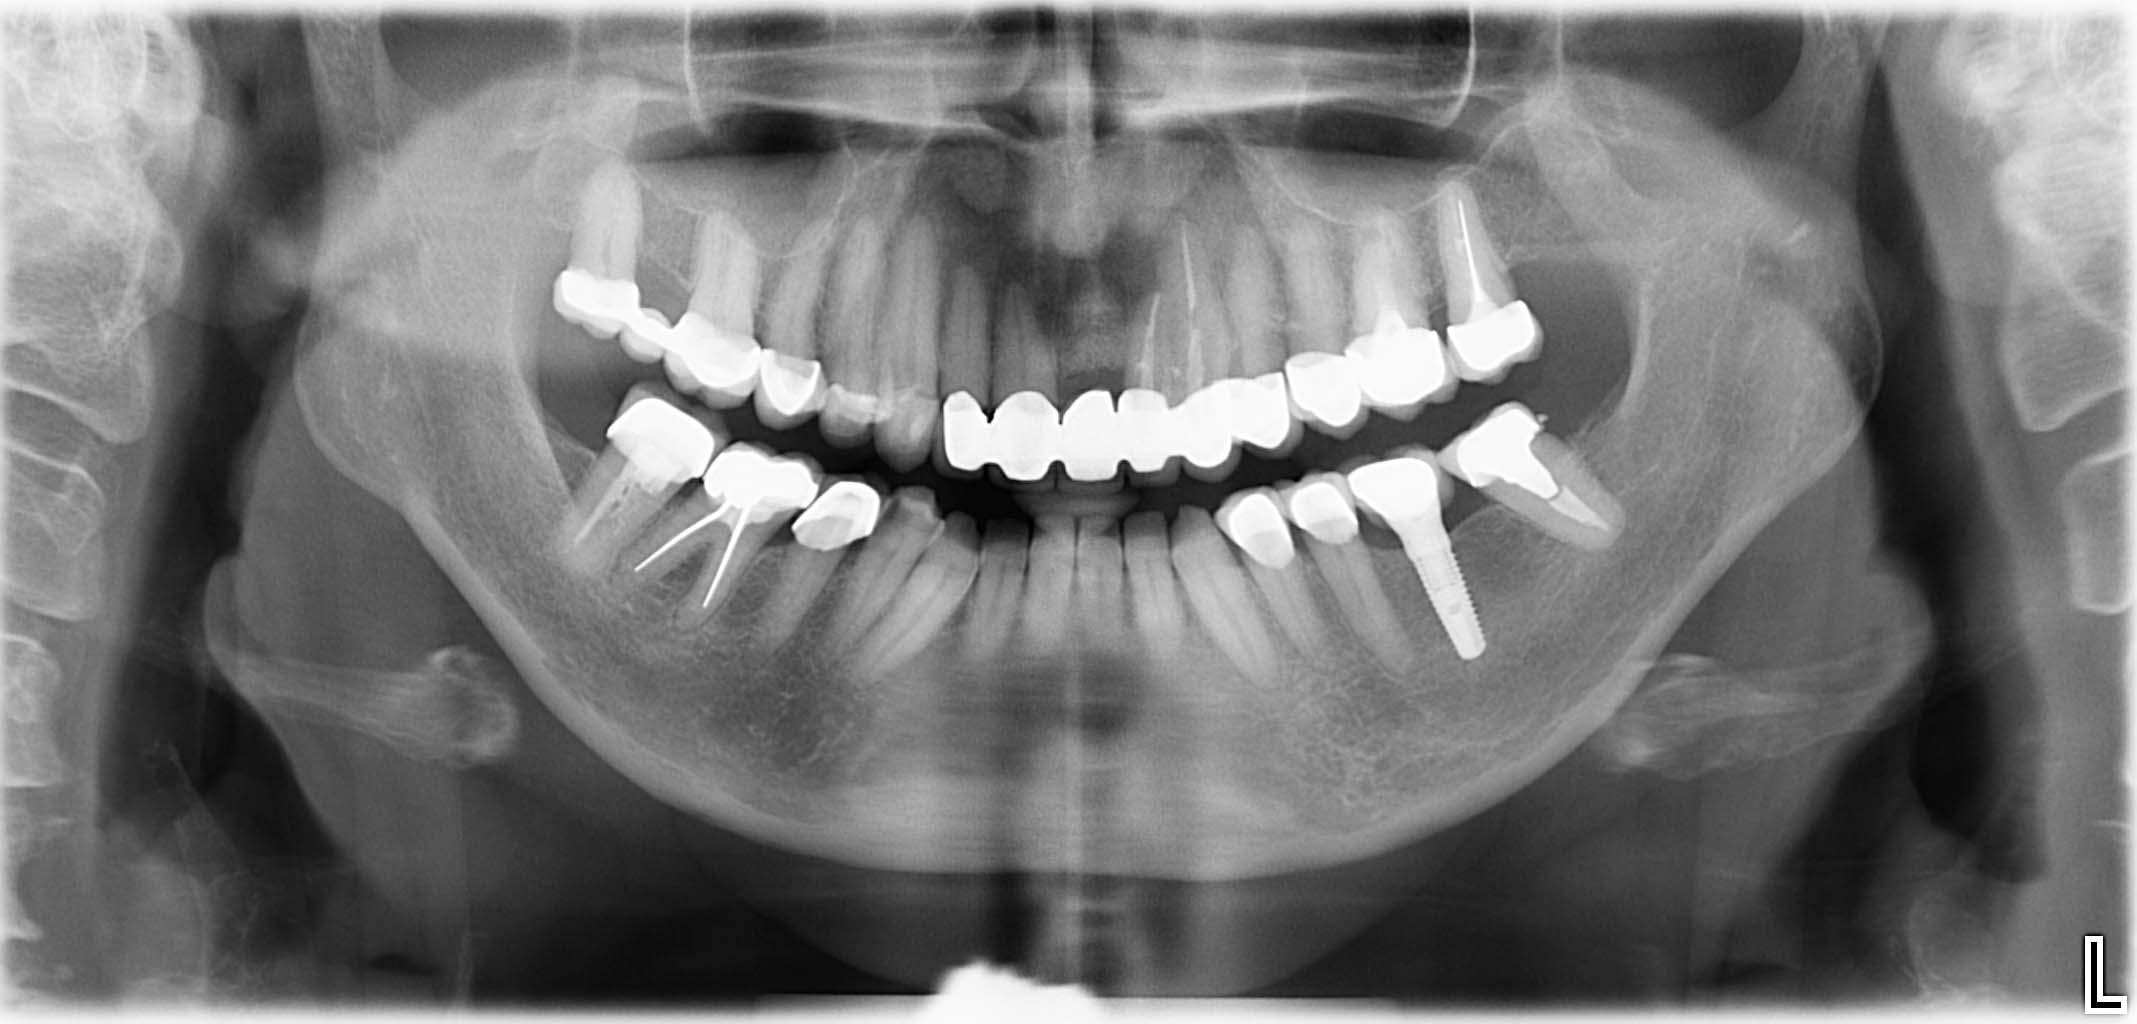

Erfolgreich implantierte Patientenfälle (klinische Fotos)